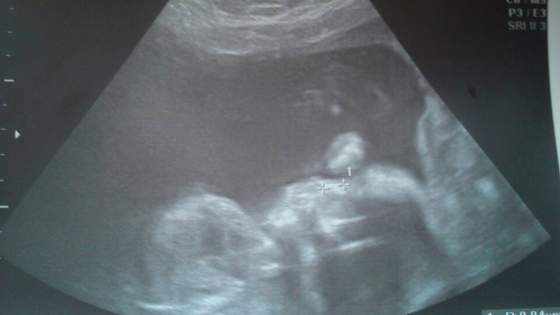

a oto i on z dzisiejszego poranka